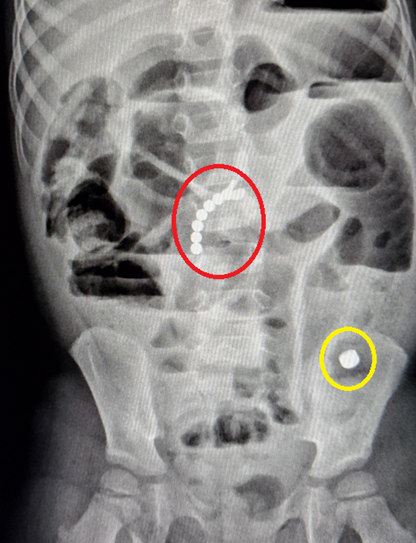

Ребёнка 3-4 лет привезли в больницу с жалобами, что ведёт себя как-то слишком беспокойно и не может сходить по большому. Целую неделю врачи ломали голову что же с ним не так, исследовали желудок и крови, но все результаты были в пределах нормы, при этом состояние только ухудшалось. Безуспешно проведя многие анализы его записали на рентген, не сильно надеясь там что-либо найти. Но именно этот рентген и оказался без преувеличения спасительным. Внутри обнаружился целый фатальный набор в виде батарейки-"таблетки" и 9 небольших магнитных шариков из конструктора-головоломки. И если батарейка при хорошем раскладе ещё могла бы выйти самостоятельно, то магнитные шарики самым неудачным образом примагнитились один к другому прямо в кишечнике и всё там заблокировали. Мало того, все эти железки начали постепенно окисляться и травить организм. В общем, если бы не этот спасительный рентген и срочная операция, в течение пары дней всё могло закончиться самым трагическим образом.

Так что, когда у вас появятся маленькие дети- будьте особенно осторожны и внимательны к мелким предметам, предостережениям на упаковках, и не недооценивайте способность детей затащить несъедобные вещи в рот.

На снимке батарейка выделена жёлтым, а магнитные шарики красным.